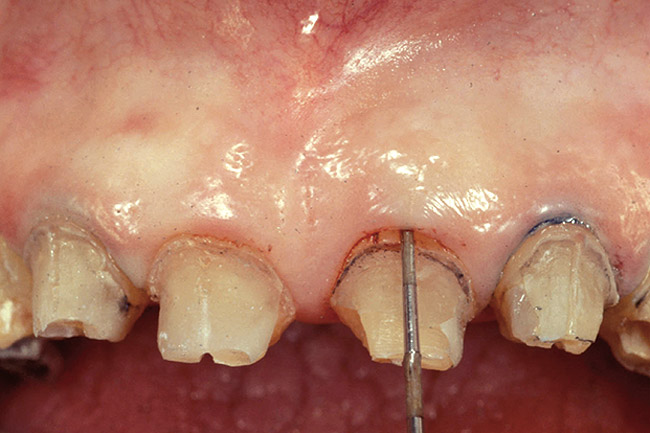

Figure 1  View of 4 porcelain veneer preparations with the margins placed at the level of tissue.

Figure 1

Figure 2  Note the invisibility of the marginal line in the completed veneers, even though the margin has not been carried below tissue.

Figure 2

A clinician is faced with 3 options for for margin placement when considering an anterior esthetic restoration: supragingival, equigingival (ie, even with tissue), and subgingival.1 The supragingival or equigingival margin will have the least impact on the periodontium and, classically, was only used in nonesthetic areas because of the stark contrast in color and opacity of traditional restorative materials. With the advent of adhesive dentistry, resin cements, and more translucent restorative materials, the ability to place supragingival or equigingival margins even in esthetic areas is now a reality (Figure 1 and Figure 2). The primary requirement of a material to enable its use in esthetic areas supra- or equigingivally is a high level of cervical translucence. Materials such as feldspathic porcelain, as well as pressable ceramics, meet this requirement. Consequently, whenever possible, these restorations should be chosen not just for their esthetic advantages, but for their favorable periodontal impact as well. The greatest biologic risk occurs when placing subgingival margins.2